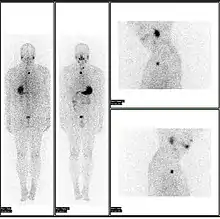

- A nuclear medicine whole body bone scan. The nuclear medicine whole body bone scan is generally used in evaluations of various bone-related pathology, such as for bone pain, stress fracture, nonmalignant bone lesions, bone infections, or the spread of cancer to the bone.